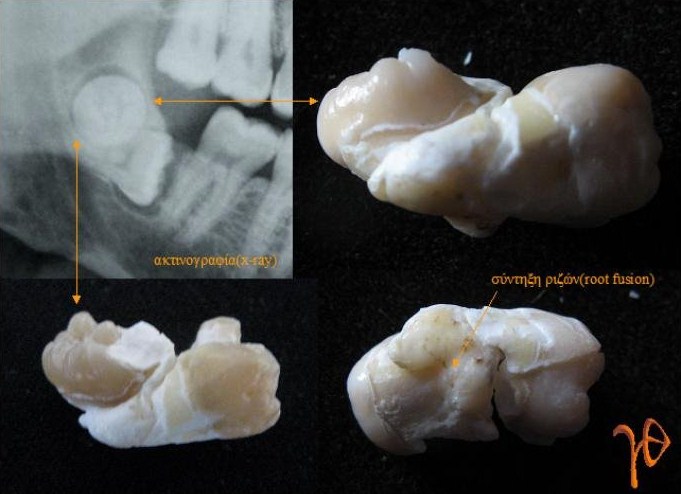

Μια περίπτωση εγκλείστου κάτω δεύτερου μόνιμου γομφίου